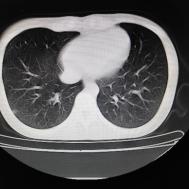

性别:女,年龄:26岁,低热,轻微胸痛,支原体阳性

[影像描述]

两肺内及胸膜下多发斑片状高密度影,部分病灶密度较淡,部分实变,边缘可见渗出改变。